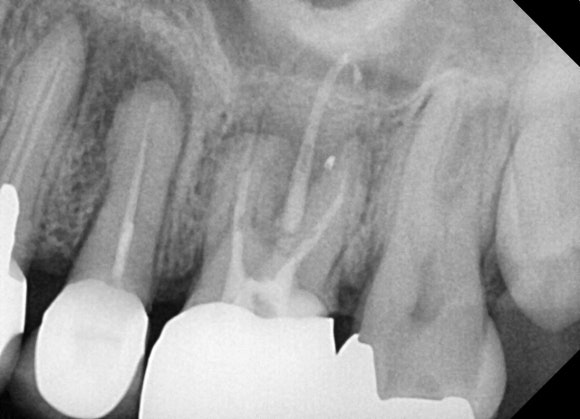

20250120

다수의 내원으로 두 치아의 재신경치료를 완료하였습니다.

치료 전 사진은 4월, 치료 후 사진은 이듬해 1월입니다.

하나씩 하나씩 진행하느라 (가장 우측에 있는 어금니도 신경치료를 진행했습니다) 시간이 오래 걸렸습니다. 총 3개의 치아를 연달아 치료해드렸네요.

가장 왼쪽에 있는 치아도 추적관찰하여

증상이 발생하면 재신경치료를 하기로 했습니다.